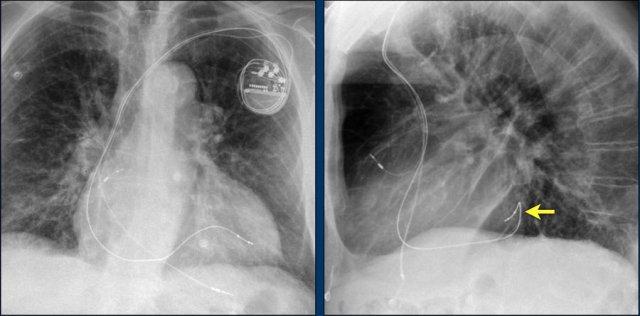

Các phát hiện bao gồm:

- Hai điện cực thượng tâm mạc kết nối với máy tạo nhịp

- ICD

- Hai điện cực đến mỏm thất phải

- Một điện cực chứa hai cuộn sốc điện

- Van ba lá (mũi tên)

- Van hai lá